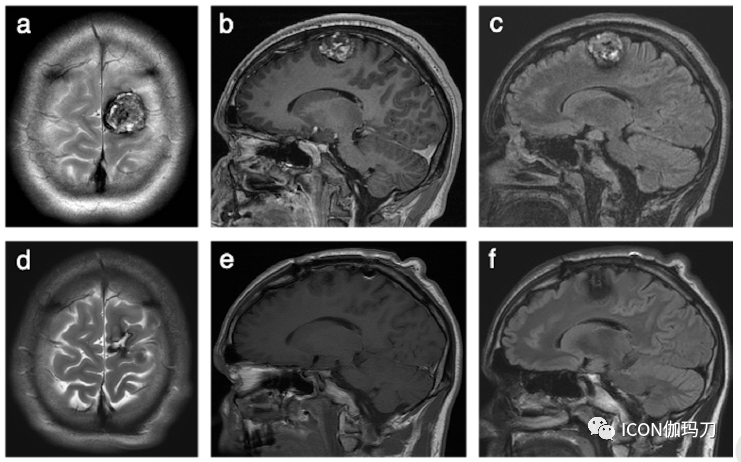

图1、所选神经影像来自15岁男性,急性头痛发作,意识模糊,双下肢无力,左侧较右侧著。在初始头部CT报告为正常的情况下,对持续的无法解释的症状进行MRI检查。(a)复查轴位DWI (b0)显示右侧额叶低信号灶。(b)轴位SWI显示低信号爆米花状病灶,在与(a)相同的位置有明显的开花现象,病灶看起来更大更明显,符合CCM。当在DWI上检测到易感性或开花伪影时,应立即获得正式的SWI,这是我们中心的常规儿科脑部序列。回顾病人先前的影像显示他在6岁时因在学校头部被撞后有过呕吐而进了头部CT检查。(c)头颅轴位CT显示右侧额叶有一个高密度的焦点(箭头),这是急性脑内出血的表现,但没有感觉。(d)审查最近的头部CT显示在同一位置确定有一个微妙的高密度局灶(箭头):病灶(c)和(d)位于相同的位置,磁共振证明为CCM。这个患者表明CCM的CT表现微妙和可能会被忽视。在报告儿童头部CT成像时,特别是考虑到脑内出血和明显的局灶神经功能缺陷的可能性,应始终存在有CCM的可能性。如(a)和(b)所示,MRI有助于诊断。

图2、16岁女性患者,双侧下部鼻侧视野 缺损,疑似颅内病变。轴位T2-WI (a)示左侧额叶小的高信号病灶,被低信号环包围(箭头),对应有矢状位T1-WI高信号(b)(箭头)。(c)轴位DWI (b0)显示相应的局灶信号缺失,即在与(a)和(b)(箭头)相同的位置出现了“开花”伪影。在毗邻左侧侧脑室枕角的脑室周围白质可见进一步低信号区域(d)(箭头),但但在同期的轴位T2-WI没有同时发生的信号异常 (e)。患者再行轴位SWI显示在整个大脑的几个区域有“开花的”伪影子(箭头)(f-h)。然而,相应的轴位幕上T2-WI(i)显示未见低信号病灶(h)。SWI时获得的轴位头部CT (j)在左侧额叶的同一位置SWI显示一个微妙的局灶高密度(箭头)(a)和(b)。(a-j)的影像特点符合多发CCMs和在多个CCMs的情况下,SWI值加强,而在其他MRI序列上不可见,或者在CT上显示不清。